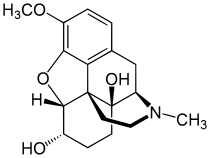

In the 19th century, two major scientific advances were made that had far-reaching effects. Around 1804, German pharmacist Friedrich Sertürner isolated morphine from opium. He described its crystallization, structure, and pharmacological properties in a well-received paper in 1817.[211][213][208][214] Morphine was the first alkaloid to be isolated from any medicinal plant, the beginning of modern scientific drug discovery.[211][215]

Several semi-synthetic opioids were developed in Germany in the 1910s. The first, oxymorphone, was synthesized from thebaine, an opioid alkaloid in opium poppies, in 1914.[228] Next, Martin Freund and Edmund Speyer developed oxycodone, also from thebaine, at the University of Frankfurt in 1916.[229] In 1920, hydrocodone was prepared by Carl Mannich and Helene Löwenheim, deriving it from codeine. In 1924, hydromorphone was synthesized by adding hydrogen to morphine. Etorphine was synthesized in 1960, from the oripavine in opium poppy straw. Buprenorphine was discovered in 1972.[228]

Opium alkaloids and derivatives

Phenanthrenes naturally occurring in (opium):

Semi-synthetic alkaloid derivatives